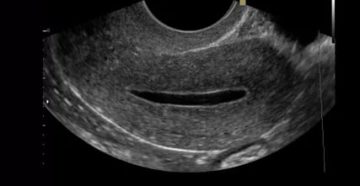

Необходимость хирургического вмешательства при анэмбрионии Проблемы с нормальным вынашиванием и последующим деторождением могут быть связаны…